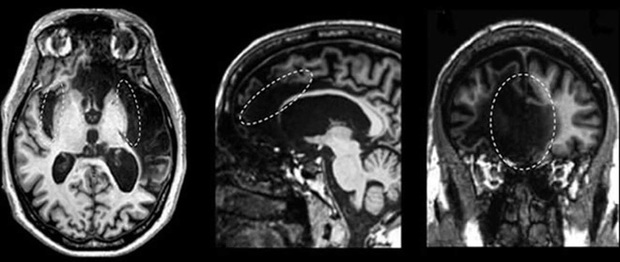

Tay-Sachs - Căn bệnh sẽ thay thế các tế bào não bằng chất béo

Tay-Sachs là một tình trạng phá hủy tế bào thần kinh và hầu như luôn gây tử vong. Đây là một căn bệnh cực kỳ hiếm gặp, nhưng ở người Do Thái Ashkenazi, người Canada gốc Đông Nam Quebec và Cajun ở miền nam Louisiana, tình trạng này phổ biến hơn. Khoảng 1 trong 3.600 trẻ em Do Thái Ashkenazi khi sinh ra sẽ bị bệnh này. Đột biến ảnh hưởng đến gen HEXA dẫn đến sự tích tụ chất béo trong các tế bào thần kinh của não, và dẫn đến các loại khuyết tật đối với người bị nhiễm.

Phiên bản nguy hiểm nhất và phổ biến nhất của bệnh này phát triển ở trẻ sơ sinh, những bệnh nhân sẽ phải trải qua một loạt các triệu chứng suy nhược. Hầu hết trẻ sơ sinh bị bệnh sẽ không qua khỏi vài năm đầu đời.